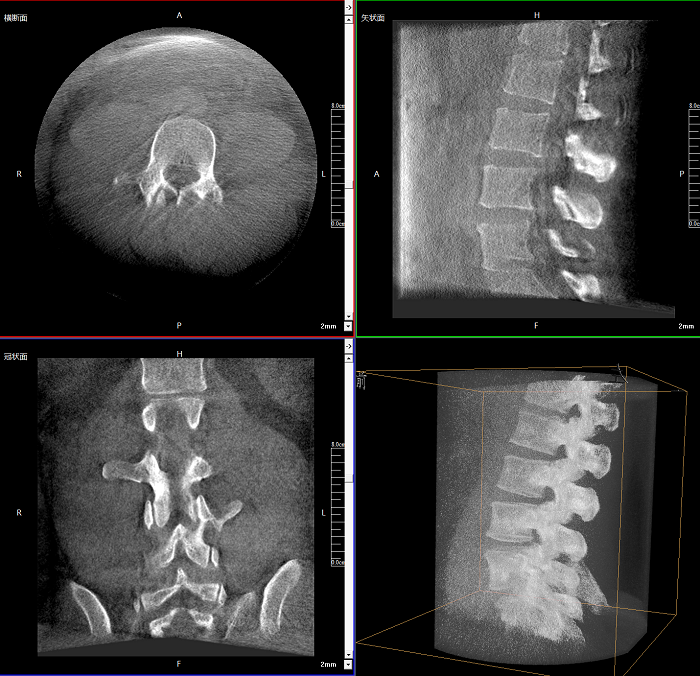

該設備可進行快速的術中三維掃描,生成類CT斷層圖像和立體3D圖像,保障植入物置入效果。廣泛適用于骨科、脊柱外科、矯形外科、創傷骨科等其他領域。

術中CT檢查 減少翻修概率

通過術中三維影像的檢查,可以立即發現植入物的錯位,減少不必要的第二次手術,減少并發癥概率以及感染風險。